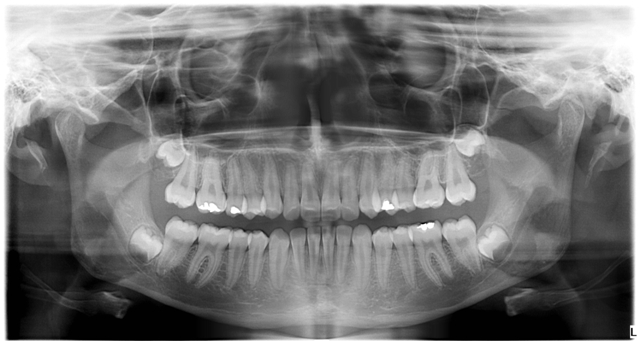

Zdjęcie pantomograficzne

Pantomogram to przeglądowe zdjęcie całego uzębienia, obejmujące również stawy skroniowo-żuchwowe oraz zatoki szczękowe. Wykonuje się je przed rozpoczęciem leczenia w celu postawienia trafnej diagnozy i wyboru najodpowiedniejszej metody leczenia, a także jest niezbędne m.in. przed leczeniem ortodontycznym i zabiegami chirurgicznymi w obrębie jamy ustnej oraz dobór odpowiednich uzupełnień protetycznych.

Diagnostyka - RTG

Nowoczesny cyfrowy aparat pantomograficzny GXDP-800 amerykańskiej firmy GENDEX gwarantuje minimalną dawkę promieni RTG i bardzo wysokiej jakości wykonywanych zdjęć.Zdjęcia można wykonać w godzinach pracy Centrum Medycznego, bez wcześniejszej rejestracji, po okazaniu skierowania.